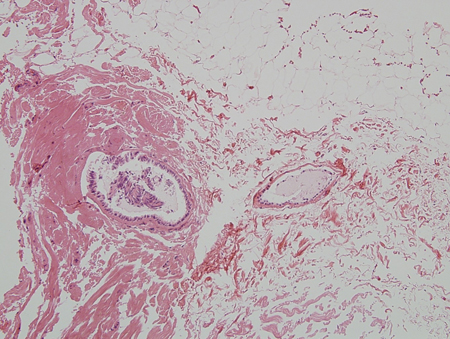

O excesso de estrogênio ou a sensibilidade aumentada ao estrogênio estimulam a proliferação de ductos mamários e de epitélio ductal. Se a deficiência de androgênio ou a inibição de androgênio estiverem presentes, o efeito do estrogênio será mais pronunciado, mesmo que o nível de estrogênio esteja normal. Na puberdade, aumentos acentuados no hormônio do crescimento, no fator de crescimento semelhante à insulina-1, no hormônio folículo-estimulante e no hormônio luteinizante estimulam a produção de estrogênio e testosterona, mas o pico de estrogênio precede o pico de produção de testosterona. Há muitos fatores que contribuem para o estrogênio elevado versus o efeito dos androgênios em adultos. Independentemente da causa, a fase inicial com a proliferação de ductos, de epitélio ductal, de estroma e fibroblastos, acompanhada por inflamação e edema, frequentemente conduz a um estágio mais quiescente caracterizado por ductos dilatados, estroma e fibrose com pouca inflamação. O estágio fibrótico tem probabilidade muito menor de regredir de modo espontâneo ou com tratamento. Os níveis de progesterona em homens são baixos e, portanto, há pouco tecido alveolar na mama masculina, mesmo quando a ginecomastia está presente. Portanto, a galactorreia é rara.[Figure caption and citation for the preceding image starts]: Histologia: mama masculina normal; ductos isolados e raros; ausência de lóbulos; ampliação de 10XDa coleção de patologia do Minneapolis Veterans Affairs Medical Center [Citation ends].

[Figure caption and citation for the preceding image starts]: Histologia: ginecomastia; aglomerados de ductos, halos de edema, base fibrosa; ampliação de 5XDo acervo de Catherine B. Niewoehner, MD [Citation ends].